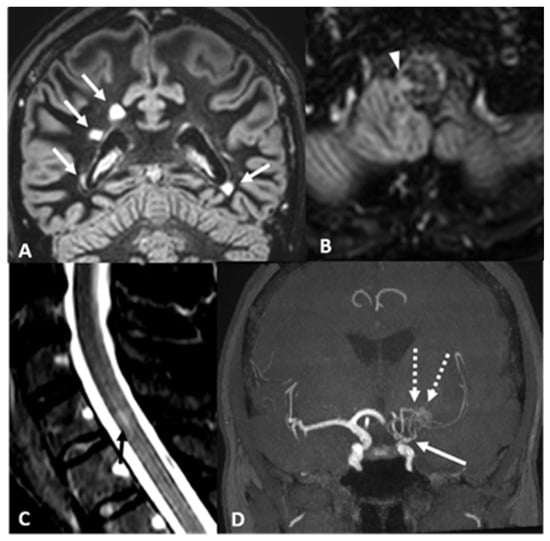

2.1. Case 1: A 45-Year-Old Woman Was Referred to Our Cerebrovascular Department for MMA

| Our Case 1 | Italy/ Caucasian | 45/F | Blurred vision and diplopia | Bilateral brainstem, left frontal and temporal lobe, right temporal lobe, cerebellar hemispheres, left periventricular region | Brain: | − | + | − | AntiAQP4 (−) Anti-ds DNA (+ 1:20) ANA-ENA-ANCA-Anti cardiolipin and beta2GP (−) | Bilateral MCAs and ACAs narrow, thick network of collateral vessels | MMA + MS | TIA | By-pass surgery, Aspirin | Corticosteroids Teriflunomide | 4 years |